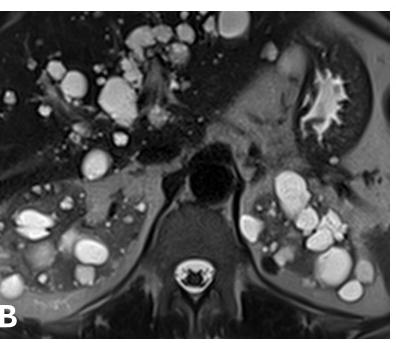

Figur 1. MR- og ultralydbilde av ADPKD nyrer. A) Koronalplan av T2-vektet MR bilde som viser lengde og bredde av nyrene hos en ADPKD pasient. B) Aksialplan av T2-vektet MR bilde av samme pasient hvor også en del levercyster er synlig øverst i bildet. C) Ultralydbilde som viser cyster med tynne septa (hvit på bildet) og væskefylt innhold (svart på bildet). Bruk av MR- og ultralydbilder fra denne pasienten er godkjent av pasienten etter innhentet samtykke (Ø. Eikrem).